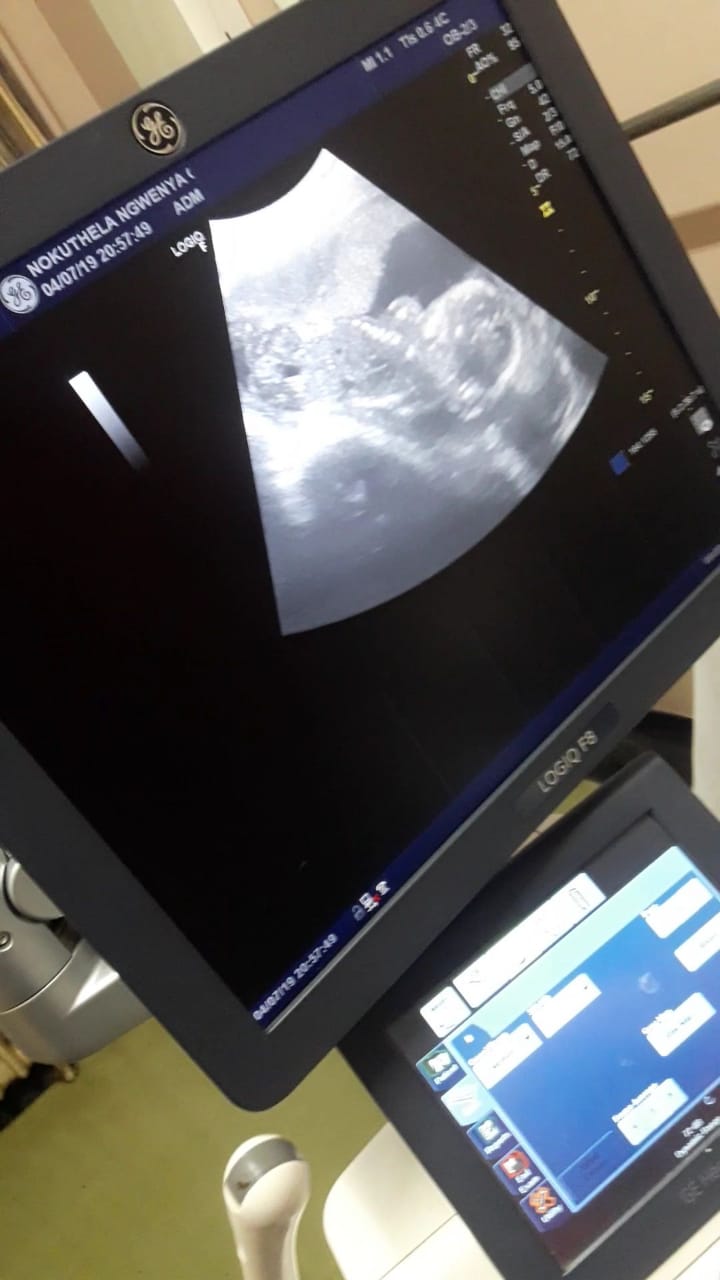

I'M PREGNANT!!!!

this year had been such a rolercoster ride and honastly I still cant believe it. It still feels like a dream that I'm just waiting to wake up from. Luckily though I haven't woken up yet and I am now 20 weeks and 5 days along with our little treasure